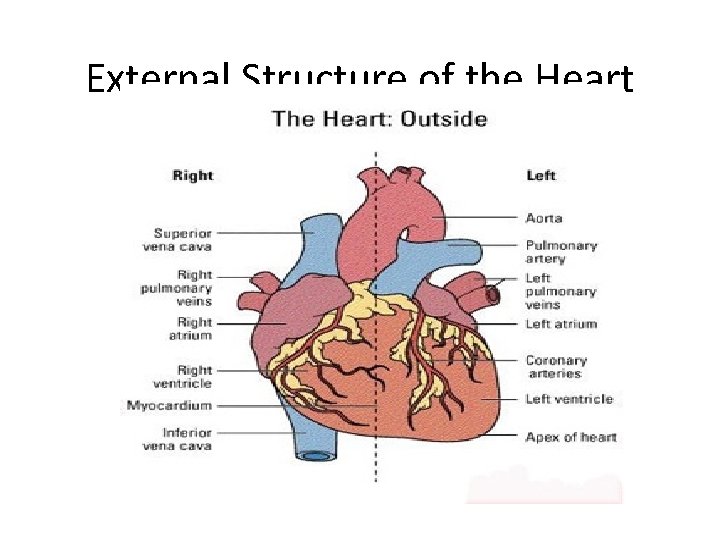

External Structure of the Heart